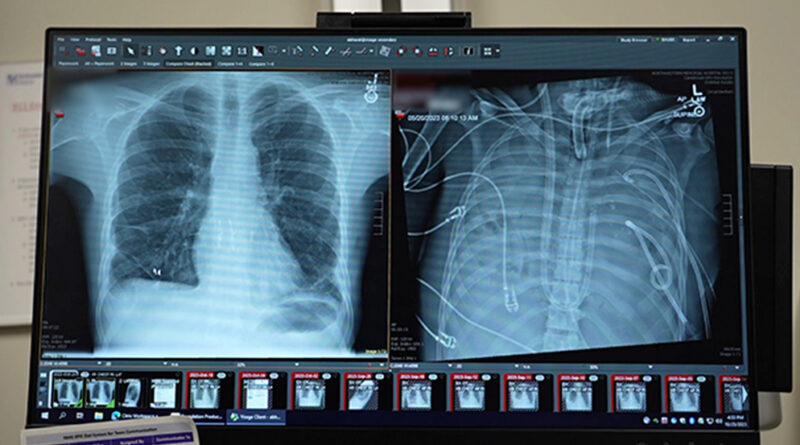

A cirurgia ocorreu em 2023, mas o caso só foi detalhado recentemente em uma publicação no periódico científico Med. O homem de 33 anos inicialmente apresentava complicações pulmonares causadas pela influenza. O quadro evoluiu rapidamente para um caso grave de pneumonia e síndrome do desconforto respiratório agudo.

As bactérias causadoras da infecção eram imunes aos antibióticos, e o estado do paciente piorava progressivamente. A função pulmonar entrou em colapso, o tecido do pulmão começou a se liquefazer, o homem sofreu uma parada cardíaca e desenvolveu insuficiência renal. Caso permanecesse com seus próprios pulmões, ele morreria.

Com essa inovação, os médicos mantiveram homem vivo por dois dias após a remoção dos pulmões. Durante esse período, sua condição apresentou melhoras significativas e o organismo começou a se recuperar da infecção, reduzindo os riscos do transplante.

Agora, três anos depois, o novo par de pulmões transplantados continua funcionando bem. O artigo que detalha o caso foi publicado em 30 de janeiro.